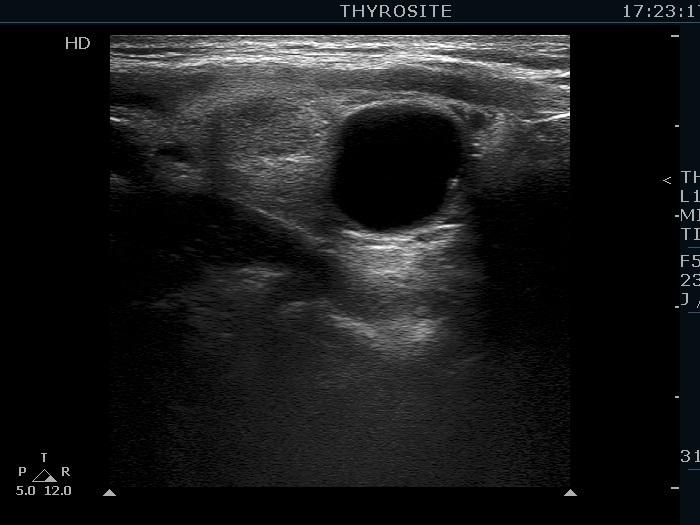

Ultrasonography. The thyroid was echonormal. There were several hypoechogenic lesions in the right lobe. The left lobe had an upper, solid and a lower cystic nodule. The former had both echonormal and moderately hypoechogenic parts and presented halo sign. The cystic nodule had a very tiny solid area in the dorsal part. Nonetheless, before aspiration it was unclear whether this would be a pure cyst or not. After aspirating 2 mL serous fluid a large, moderately hypoechogenic solid area replaced the previous cystic field and it became evident that this is in fact a central type cystic nodule.